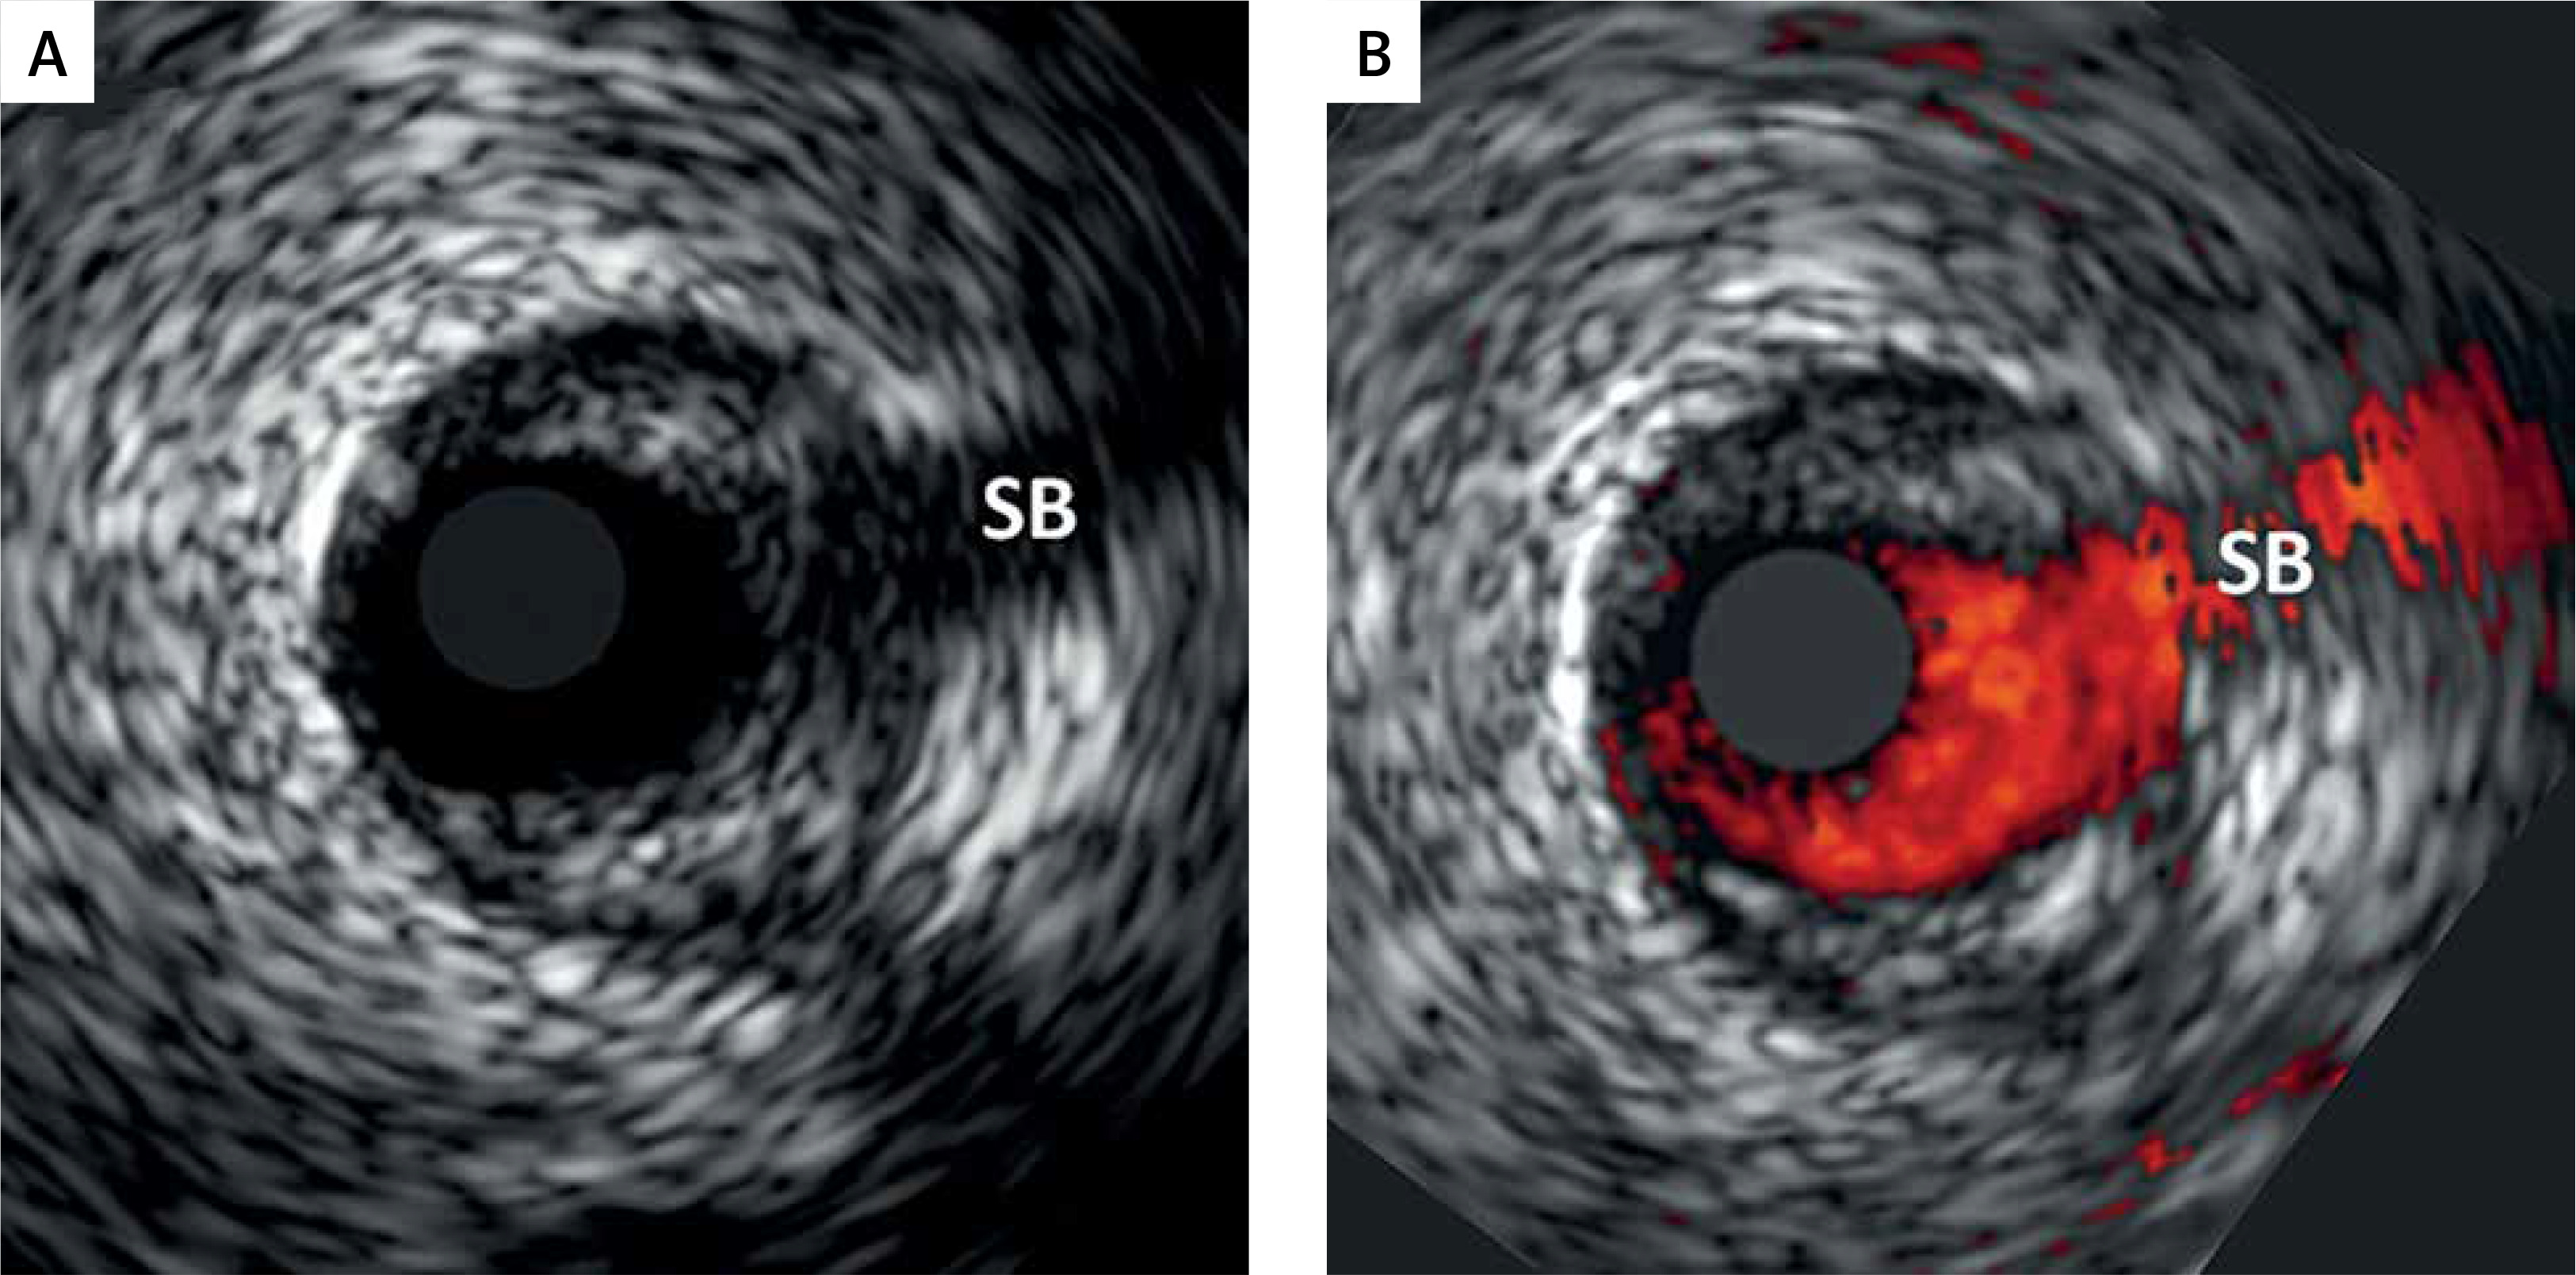

Figure 2

An illustrative example of fundamental importance of performing a matched-image (gray-scale IVUS/VH, A, and ChromaFlo, B) combined analysis to improve accuracy of the plaque luminal border delineation and ensuring same-spot analysis at baseline at follow-up. As the plaque luminal border may not be easy to determine (example in A), matched-image analysis, we introduced a routine application of a “matched image” analysis within the qVH algorithm [21]. This enables minimization of errors in plaque content quantification by VH analysis, that is critical for quantitative evaluation of the plaque composition, and in particular for the qVH measurement of fibrous cap thickness, cf. Figures 1 and 3). “Matched image” analysis plays also an important role in a longitudinal study of plaque evolution that requires a plaque image capture in the same spot (note side branch, SB, as a landmark, to minimize the likelihood of erroneous detection of a change in plaque characteristics as a result of a change in the sampling site along the arterial lumen) [28]